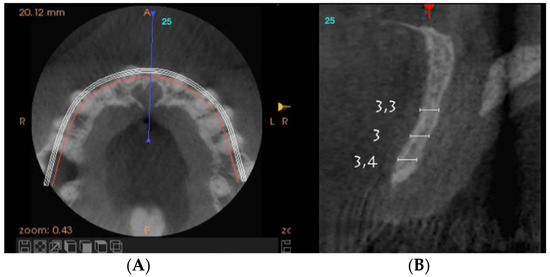

On clinical inspection of the aesthetic area, it was observed in all patients that the integrity of the vestibular plate was compromised by significant physiological and structural changes after extraction (Figure 1). This was verified through periapical radiographs and/or panoramic and dental CBCT, which provided sagittal and frontal slices for analysis. On sagittal CBCT images, the anteroposterior distance of the CNP at the level of its upper, middle, and lower thirds was calculated. Axial plane images were in turn used to determine NPC height from the level of the upper bifurcation to the palatal opening, and the width of the residual crest in the toothless zone [24,25].

Axial sections corresponding to the middle part of the NPC showed the collapse of the vestibular plate and revealed the conduit’s size. All the cases presented thinning of the palatal ridge due to marked widening of the incisive foramen (Figure 2); so, according to the SAC Classification (i.e., simple, advanced, or complex), they were categorized as complex [2]. In addition, careful consideration had to be given to the nasopalatine bundle for correct three-dimensional positioning of the implant. Since the vertical and horizontal defects demanded bone augmentation before implant placement [17], a diagnostic wax-up was performed to determine the amount of bone needed in each case.

Figure 2.

Representative sections of a Cone Beam Computed Tomography (CBCT) scan in which the bone thickness of the maxillofacial region and the widening of the incisive foramen are observed. (A) Occlusal view. (B) Sagittal view.

For each patient, pre- and post-treatment CBCT measurements of the anterior ridge thickness of the aforementioned foramen were taken at different heights, i.e., 4, 8, and 14 mm apical to the marginal bone ridge. CBTC was performed at 90 Kv and 10 mA, with an 18-second exposure cycle on a Promax-3D plus equipment (Planmeca, Finland). The obtained images were analyzed with Romexis 4.4.0.R. A field of view of 40 mm by 50 mm was used, with an isoropic voxel size of 75 µm (0.075 mm). Serial slices (0.5 mm in thickness) with 0.5 mm reconstruction intervals were analyzed.

For the scanning procedure, the occlusal planes were oriented parallel to the horizontal plane. Medical imaging recording protocols were used for comparative measurements. First, image relationships were determined following the process of superimposition of tomographic images obtained by CBCT by using the Canny edge detection module of MATLAB R2018a (64-bit). Overlays were made in the areas of interest, obtaining identical reference points as those provided by the Canny filter.

For each patient, pre-surgical measurements were taken in the vestibular table observed from the sagittal plane, from the vestibular cortex to the anterior cortical wall of the NPC. In the same fashion, the vestibulo–palatine width was measured between 6.5 and 9.5 months (7 months on average) after implant activation.

Pre-surgical vestibulo–palatine width (mean ± standard deviation) of the anterior ridge at different heights (4, 8, and 14 mm apical to the marginal bone ridge) was 3.5 ± 2.0 mm; 5.4 ± 1.5 mm, and 6.1 ± 1.9 mm, respectively. Post-treatment total vestibulo–palatine width was 10.1 ± 2.0 mm, 10.5 ± 1 mm, and 13.4 ± 3.0 mm, respectively (Table 4).